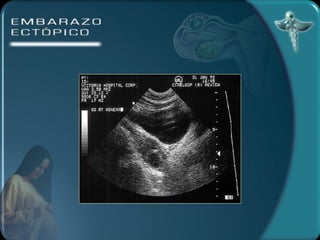

DIAGNÓSTICO Por imagen Ecografía transvaginal útero vacío 100% tumor parauterino 85 % embrión 55% Anillo tubárico Líquido en el fondo del saco

DIAGNÓSTICO Por imagenEcografía transvaginal útero vacío 100% tumor parauterino 85 % embrión 55% Anillo tubárico Líquido en el fondo del saco

• #23 DIAGNÓSTICO )LABORATORIO: la hemoglobina y el hematocrito pueden ser de utilidad para el seguimiento de la paciente. Estos valores pueden no alterarse precozmente ante una hemorragia.La leucocitosis puede estar presente en el 50% de los casos mientras que el otro 50% permanece con valores normales.La gonadotrofina coriónica humana puede investigarse en suero o en orina. Las pruebas urinarias son de poca sensibilidad en esta patología. Con la prueba de ß HCG en suero se puede detectar todo tipo de embarazos. Los niveles de la ßHCG se correlacionan con la edad gestacional. Durante las primeras 6 semanas de gestación los niveles séricos se incrementan en forma exponencial ( la duplicación del valor de la ßHCG es constante), después de las 6 semanas (nivel de la ßHCG de 6000 a 10000 mUI/ml) el ascenso se hace más lento y menos constante. Cundo los niveles de ßHCG son bajos (por debajo de 1000 mUI/ml) el valor absoluto es menos útil para diferenciar un embarazo normal de uno extrauterino. 2) ECOGRAFÍA TRANSABDOMINAL A) ÚTERO VACÍO B) MASA ANEXIAL C) LÍQUIDO EN EL FONDO DE SACO Con este método no es posible diagnosticar embarazos pequeños de 5 a 7 semanas. 3) ECOGRAFÍA TRANSVAGINAL A) ANILLO TUBÁRICO: un anillo ecogénico alrededor de un centro hipoecogénico como estructura encontrada fuera del útero. B) LÍQUIDO EN EL FONDO DE SACO Este método permite un diagnóstico precoz del embarazo ectópico 4) CULDOCENTESIS: se realiza cuando se detecta una colección líquida en el saco de Douglas. 5) LAPAROSCOPÍA: permite establecer el diagnóstico definitivo.